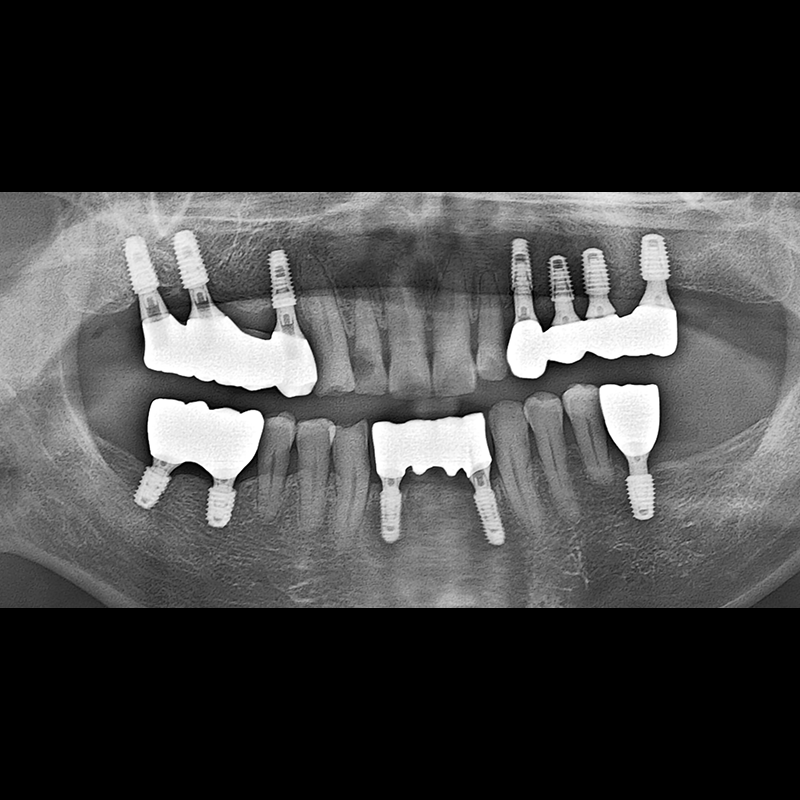

BEFORE AFTER

Implant before and after 2025.05.30

Implants were placed in the missing tooth and in the tooth position where it was difficult to save.